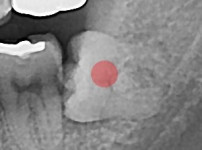

충치가 심한 사랑니

조회

876

작성일

25-12-03